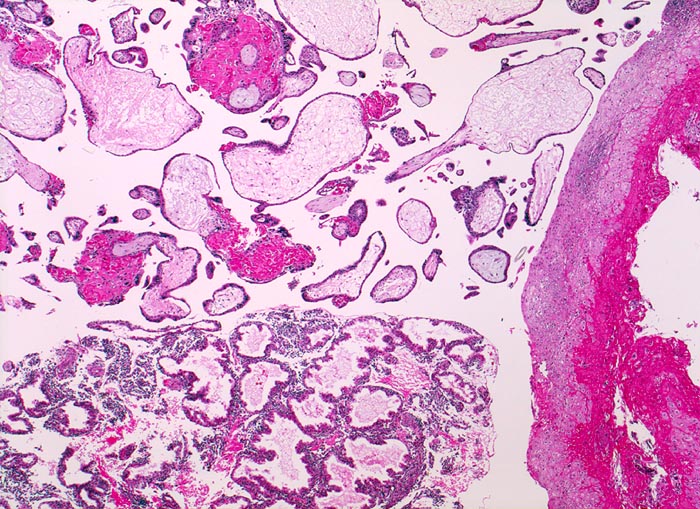

Chromosomenaberrationen verursachen nicht nur beim Feten, sondern auch an der Chorionzotte morphologisch fassbare Entwicklungsstörungen: mangelnde Verzweigungen, wandernde Trophoblastzellen im Stroma, mangelhafte Vaskularisation, hydropische Alteration des Stromas und herdförmige Atrophie oder auch Hyperplasie des Trophoblasten sind typische Befunde bei einer Chromosomenaberration. Aborte mit Triploidie zeigen in der grossen Mehrzahl das Bild einer Partialmole. Eine Tetraploidie kann das Bild einer Windmole (=Windei), einer Embryonalmole oder seltener einer Partialmole verursachen. Autosomale Trisomien können ebenfalls als Windmole oder als Embryonalmole imponieren. In nur etwa 25% aller Spontanaborte sind bei der pathomorphologischen Untersuchung ein Embryo, Embryofragmente oder ein Nabelschnuranteil nachweisbar. Die morphologische Untersuchung des Abortmaterials stellt eine wichtige Ergänzung zu den klinischen Befunden dar.

• Vergrösserte Plazentarzotten mit hydropischem Zottenstroma.

• Vereinzelt Zytotrophoblasteinschlüsse im Stroma.

• Vorwiegend einschichtiges Zytotrophoblastepithel ohne Atypien und mehrkerniger Synzytiotrophoblast. Physiologische polare Trophoblastproliferate.

• Kein Embryo.

• Keine Anteile der Dezidua.